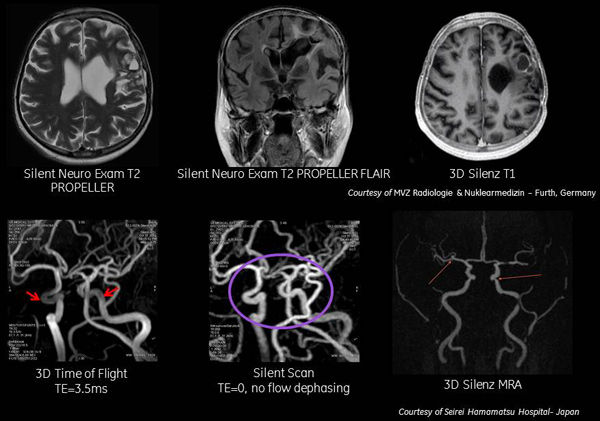

A Quieter, Productive Experience – “GE Silent Scan Expands to More MRI Sequences; Enables Fully Silent Neuro Scan”

If you ever had an “MRI” as part of a yearly physical examination, you know how noisy the equipment can be.  The doctor may have offered earplugs to reduce the knocking sounds. Times have changed for the better.  Medgadget reported how innovation has improved for the patient and doctor.